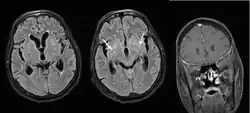

Cryptococcal meningitis (infection of the meninges, the tissue covering the brain) is believed to result from dissemination of the fungus from either an observed or unappreciated pulmonary infection. Often there is also silent dissemination throughout the brain when meningitis is present. People with defects in their cell-mediated immunity, for example, people with AIDS, are especially susceptible to disseminated cryptococcosis. Cryptococcosis is often fatal, even if treated. It is estimated that the three-month case-fatality rate is 9% in high-income regions, 55% in low/middle-income regions, and 70% in sub-Saharan Africa. As of 2009 there were globally approximately 958,000 annual cases and 625,000 deaths within three months after infection.[27]

Cryptococcal meningitis